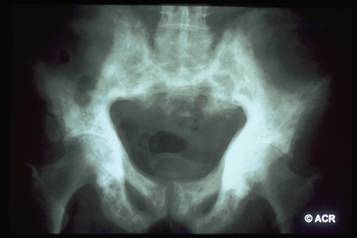

Reperti radiografici

Lisi ossea: riflette l'aumentata attività osteoclastica;

Sclerosi: riflette l'aumentata attività osteoblastica;

Aumento volumetrico dell'osso;

Lesioni litiche a "fiamma": riscontrabili a carico delle ossa lunghe;

Utile anche la scintigrafia ossea: può aiutare nel determinare l'estensione del coinvolgimento osseo, tuttavia non dovrebbe essere usata per porre diagnosi.